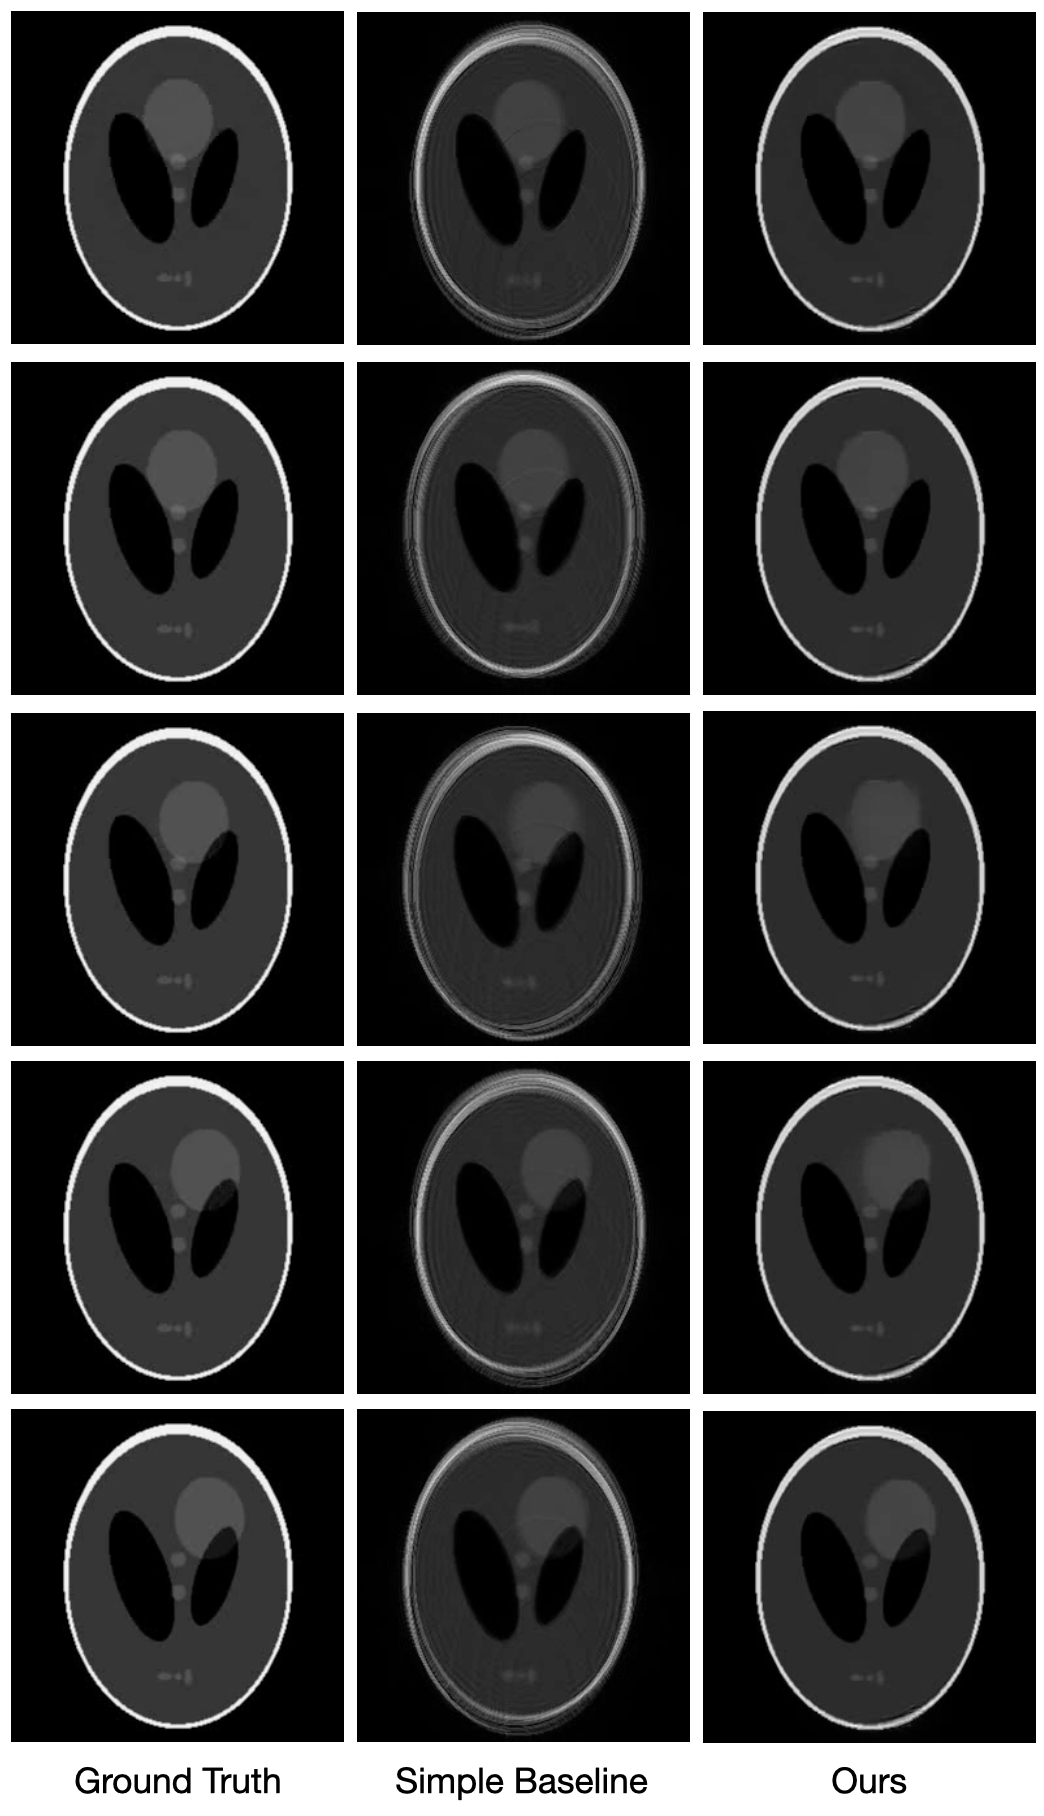

Static Shepp–Logan dataset.

Our static synthetic results are shown in Figure 6, in which we compare our reconstruction of the classic Shepp–Logan phantom with a simple baseline reconstruction. The baseline recovers the basic structure of the Shepp–Logan phantom, but suffers severe off-resonance artifacts most visible around the bright outer ellipse, which simulates fatty tissue that is most susceptible to chemical shift. Our reconstruction is free of these off-resonance effects and successfully combines the five undersampled blade measurements into a single clean image.